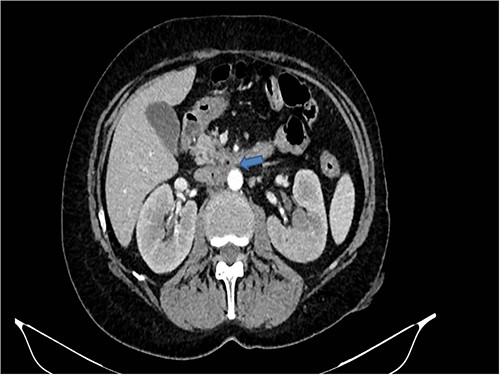

Therefore, given the persistence of the septic state and the radiological findings, the patient underwent laparotomy. Dense retroperitoneal fibrosis surrounded the IVC and the third section of the duodenum (Fig. 3). After complete mobilization of the duodenum with exposure and preparation of the entire subhepatic inferior caval vein and the two renal veins, the duodenal incision located at the level of the posterior wall of its third portion and the caval vein were sutured (Fig. 4). The cholecystectomy with Kehr drainage placement to protect the bowel suture and a jejunostomy were performed.

The intraoperative finding confirms the location DCF at the third duodenal portion.